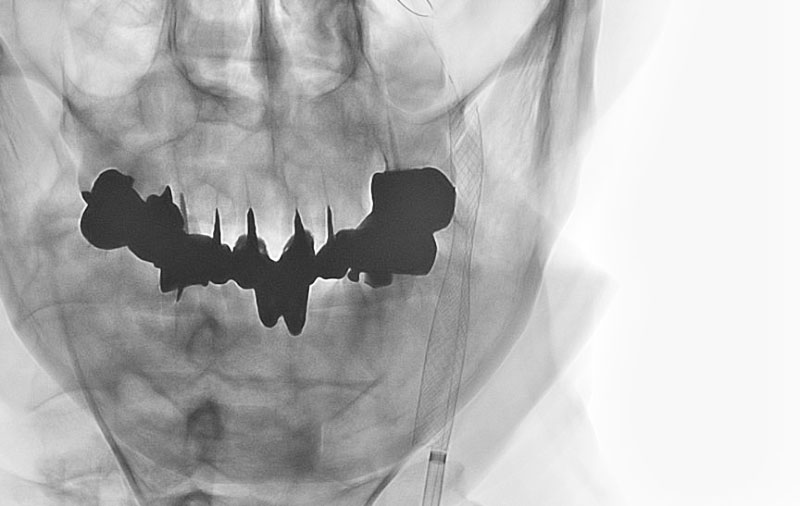

'25年10月

左総頚動脈狭窄症

30代

院内外来

No.1590 手術前

No.1590 手術中

No.1590 手術後